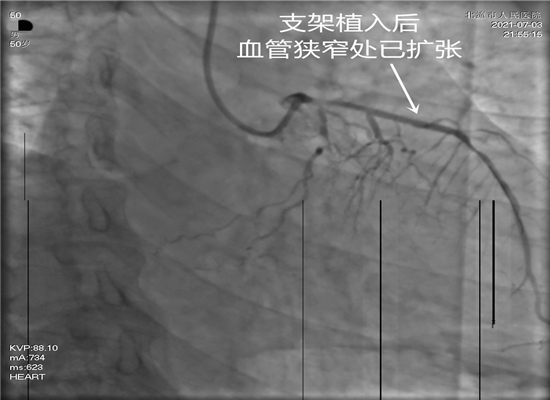

支架植入后血管狭窄处已扩张